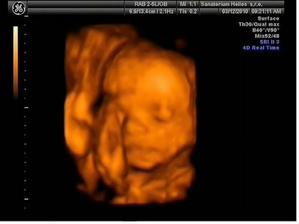

*17.2.10 ultrazvuk v 21tt + kardio ultrazvuk - vše úplně ukázkové :o) hurááá a vypadá to na holčičiku - první Dr. neviděl nic, byla zavrtaná prckou do měkkého a při vyšetření srdíčka se mrkl druhý pan Dr. i mezi nožky a říkal, že vidí holčičku, tak mu to budeme věřit :o) Večer manžel cítil kopanečky na bříšku, bylo to moc pěkný :o)